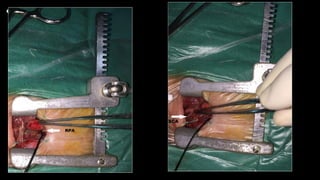

• All MBT shunt procedures were performed via upper

ministernotomy. A small skin incision was made from 0.5 cm

below the suprasternal notch to 1 cm below the sternal

was dissected.

• The systemic site of the shunt insertion was either the innominate or right

subclavian artery, and the site of the distal anastomosis was the right

pulmonary artery as close to the middle line as possible.

• The systemic artery was partially clamped with a Cooley clamp, and a

longitudinal arteriotomy was performed at the undersurface of the artery.

A transversely cut polytetrafluoroethylene (Gore-Tex) tube graft (W. L.

Gore & Associates, Inc., USA) was sutured end-to-side to the arteriotomy.

The clamp was then released in situ to ensure good shunt flow and a

competent anastomosis. The systemic artery was clamped again, and the

shunt was flushed by heparinised saline to flush any thrombi, then the

shunt was trimmed to the appropriate length. The right pulmonary artery

was partially clamped with a Cooley clamp, and an end-to-side distal

anastomosis was performed in the same way All neonates in this series

received 3.5-mm grafts, and the ductus was not ligated.